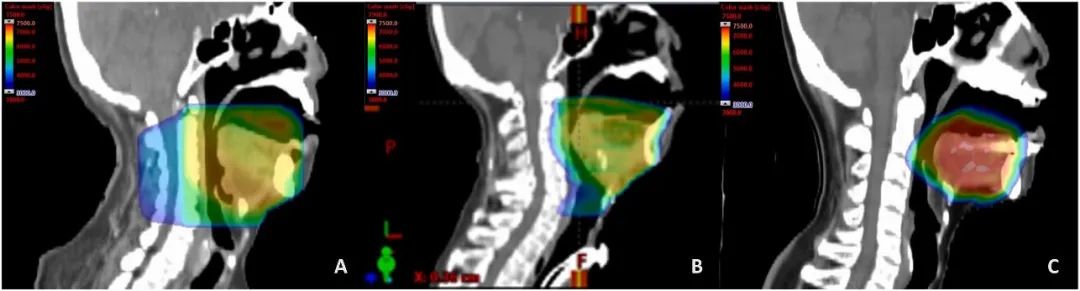

下图分别展示了病例1、2和3的辐射剂量分布情况。插入定位器械时,舌头被压低。20 mm的开口使硬腭、软腭和上颌骨突远离辐射区域。与3D-CRT相比,IMRT和IMPT向双侧腮腺和下颌骨后部输送了较低的辐射剂量。

在接受放射治疗期间和治疗过程中,患者在家中使用口腔器械进行肌肉锻炼。每周评估中观察到放射治疗的轻度不良反应。患者出现了0-1级的口干和体重减轻。第1位患者在第4周表现出3级的放射性口腔黏膜炎,而第2和第3位患者分别经历了1级和2级的放射性口腔黏膜炎。没有患者出现腭黏膜炎。